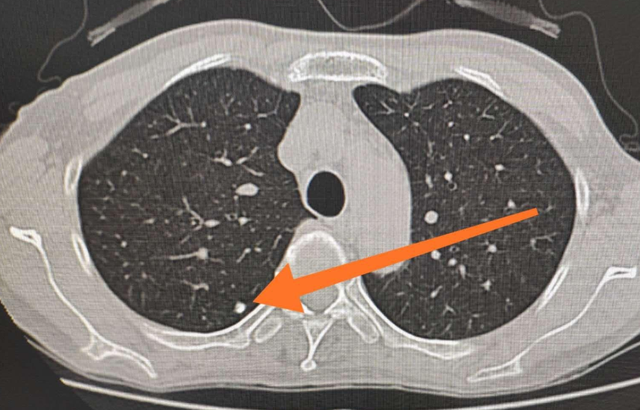

肺部结节可单发或多发,按结节密度分为实性结节、部分实性结节和磨玻璃密度结节。不同密度的肺结节,其恶性概率不同,其中,部分实性结节的恶性概率最高,其次为磨玻璃密度结节和实性结节。

局部病灶直径<5毫米的称为微小结节,直径5~10毫米的称为小结节,直径≤30毫米的称为肺结节,直径>30毫米的称为肺肿块,肺癌的可能性相对较大。

过去体检是拍胸部X光片,但X光片难以发现小于10毫米的结节;如今大多采用胸部低剂量CT检查,在肺内病变中的诊断优势非常明显:CT通过显示组织横断面及三维结构图像进行诊查,有效避免了肺与心脏、纵隔、横膈等组织的重叠,能发现肺尖、脊柱旁、靠近胸膜、心脏后方等部位胸片难以发现的病灶。

如果胸部CT检查提示肺部结节大于10毫米,或者复查结节有明显的增大,边缘有毛刺和分叶的情况,则考虑恶性的可能,需要尽早进行手术切除治疗。